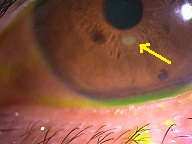

?青の部分の網膜が、視野の中心部の視界を担うようになります。

赤に比べて、青の網膜は、視細胞の数も能力も乏しくなります。この青の網膜が中心部の見え方を担当するようになるので、どんなに回復しても「視力が悪い」、「感度が悪い」、「少し暗く見える」などが残り、完全に元通りという事はあり得ないのです。

また、中心部にギュッと網膜を引き寄せた感じになるために、基本的には「ゆがむ」「物が小さく見える」などの症状も残ります。